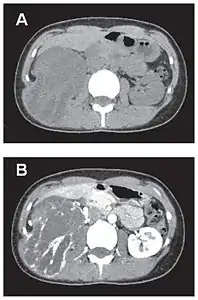

- Tumeur fibreuse solitaire du rétropéritoine

Aspect tomodensitométrique, sans (A) puis avec (B) injection de produit de contraste[44].

Aspect IRM, en séquence T1 (A) et T2 (B)[44].